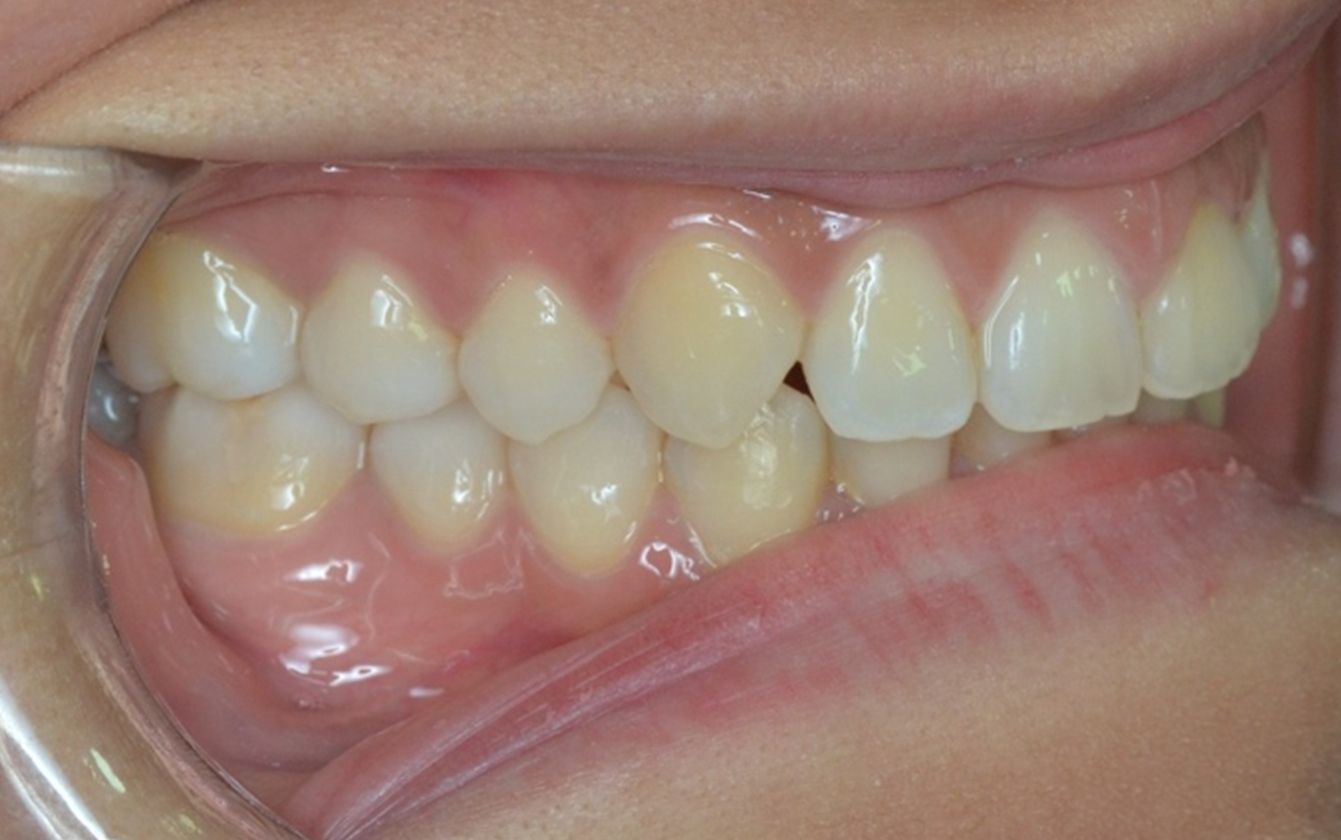

A continuación, mostramos el caso de una paciente adulta con clase II ósea y dentaria.

Con Ortodoncia Invisible, y gracias a la cooperación de la paciente, conseguimos este resultado y, lo más importante de todo, que la paciente sonría sin complejos.